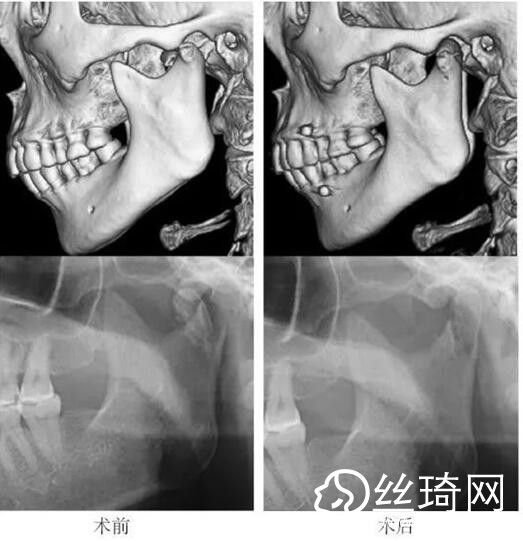

在106側(cè)中,髁突高位矢狀骨折46側(cè),中位髁頸骨折26側(cè),低位髁頸下骨折34側(cè)。髁突高位矢狀骨折及中位髁頸骨折均經(jīng)耳屏前徑路復(fù)位;34側(cè)低位髁頸下骨折中,經(jīng)耳屏前徑路復(fù)位13側(cè),頜下徑路復(fù)位19側(cè),頜后徑路復(fù)位1側(cè),穿腮腺徑路復(fù)位1側(cè)。髁突高位矢狀骨折復(fù)位后以1~2枚可吸收長螺釘固定(圖1)[3],采用的可吸收內(nèi)固定系統(tǒng)為BioSorb(ConMed Linvatec,芬蘭)、Inion OTPS(Inion,芬蘭);規(guī)格:直徑2 mm,長度15~20 mm。中位髁頸骨折及低位髁頸下骨折多以2塊可吸收板固定(圖2)[3],個別病例以1塊或3塊可吸收板固定,采用的可吸收內(nèi)固定系統(tǒng)為BioSorb(ConMed Linvatec,芬蘭)、Grand Fix(Gunze,日本)、Inion OTPS(Inion,芬蘭);規(guī)格:直4孔板,孔徑 mm或2.5 mm,長度21~35 mm,螺釘直徑 mm或2.5 mm,長度7~10 mm??晌蔗敯宓氖中g(shù)操作采用專用器械工具盒,并遵照廠家操作指引進(jìn)行。

本組病例中,絕大多數(shù)髁頸、髁頸下骨折均經(jīng)耳屏前或頜下切口進(jìn)行復(fù)位固定,均獲得了良好的復(fù)位固定性及療。有2例患者輕度移位,可能與過早承重及可吸收材料的強(qiáng)度較弱有關(guān)。